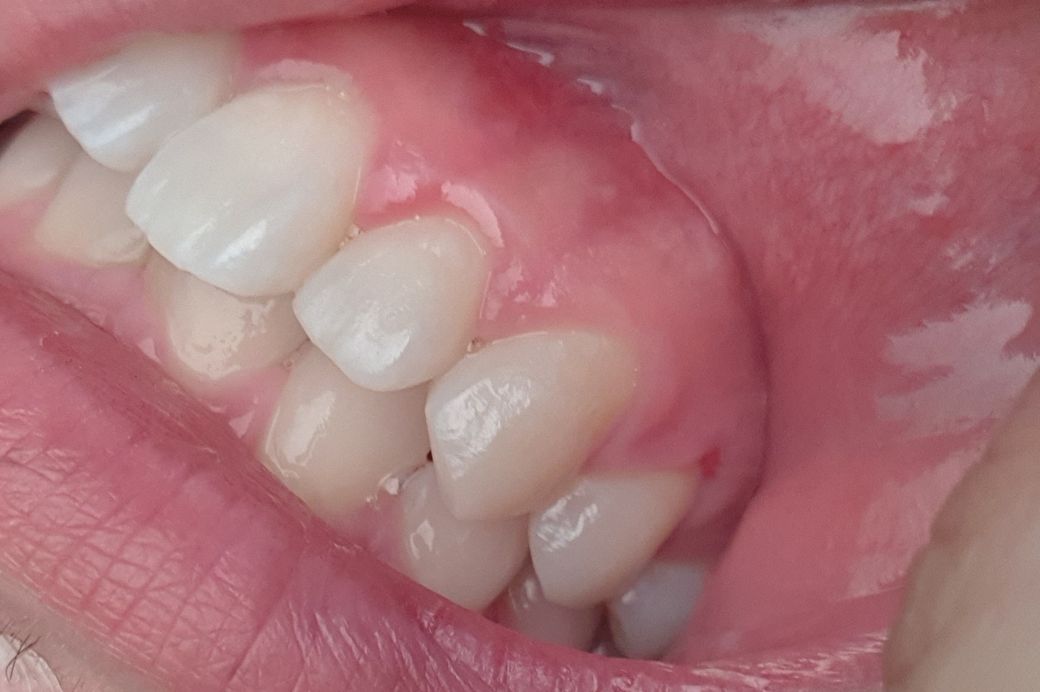

하루 뒤 양치하는데 윗 잇몸 앞니에서 오른쪽 두번째 위가

아프더라구요 혀로 만지면 뭔가 살짝 묘하게 튀어나온 느낌?

왼쪽위 작은어금니 쪽에 살짝 상처가 잇는거 같습니다. 그쪽부위에 염증이 잇어서 스켈링을 쫌 강하게 하신거 같네요. 크게 문제가 잇거나 그렇진 않습니다.

사진 상으로는 건강한 잇몸으로 보이기 때문에 일시적인 증상으로 생각되며 증상이 계속되면 해당 치과선생님께 여쭤보세요